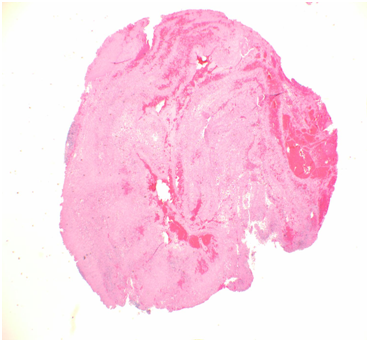

A 57-year-old white male patient with known history of coronary artery disease, morbid obesity, obstructive sleep apnea, hypertension, hyperlipidemia, atrial fibrillation, and tobacco use, presented to a local emergency room with a sudden sharp right arm pain, followed a few hours later by numbness of the right hand. His physical exam was normal except for a very weak pulsation of the right brachial artery. His initial workup included a normal chest x-ray with no acute cardiopulmonary process. A doppler ultrasound of the right upper extremity indicated thrombosis with near-complete occlusion of the distal right brachial artery. He was urgently seen by vascular surgery and underwent thrombectomy of the distal right brachial artery thrombus that was sent for pathology. Hematoxylin Eosin stain and Grocott’s methenamine silver stain showed fungal organisms identified at the thrombus, that had thin septate hyphae with regular branching and that were morphologically consistent with Aspergillus species (Figures 1-6). Subsequently, he was started on intravenous voriconazole, after his EKG, liver function tests were evaluated revealing a normal QTc interval, and liver enzymes respectively. Patient was then evaluated for evidence of disseminated Aspergillosis. His blood cultures have been negative. Aspergillus galactomannan antigen was negative, and his HIV ½ Antibody screen was negative. A computed tomography (CT) scan of the chest with angiography showed an ascending aortic pseudoaneurysm with large soft tissue component, representing a mycotic aneurysm. The contrast opacified lumen of the pseudoaneurysm measured 2.8 x 3.8 cm and there was a portion of the pseudoaneurysm more superiorly that was thrombosed measuring 6.3 x 7.2 cm (Figures 7 & 8). His lungs were clear without evidence of pulmonary nodules or consolidation. CT scan of the brain with contrast and a complete ophthalmological examination were unremarkable. Transthoracic and transesophageal echocardiograms showed no major cardiac finding and no evidence of valvular vegetations. He was then transferred to a tertiary care center where he underwent a homograft of cryopreserved human tissue given the fact that he has an infected mediastinum. He was continued on Voriconazole orally, and he will receive it for life.To note that, five years prior to this event, he underwent an urgent coronary artery bypass grafting (CABG)X3 with reversed autogenous saphenous vein graft from the aorta to the left anterior descending artery, from the aorta to the ramus intermediate, from the aorta to the obtuse marginal artery, along with endoscopic vein harvest left and right greater saphenous veins (from knee to groin bilaterally).

Figures 4-6 GMS stain showing the same findings.